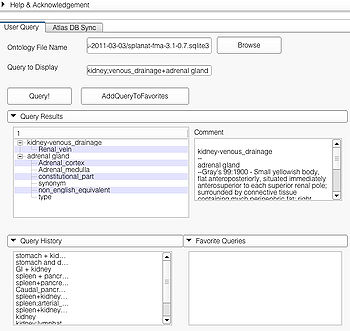

User Query Page

This page is useful for creating visualizations based on user typed queries. The user inputs consist of the Ontology File Name and Query To Display. The button Query fires a query and causes the module to start processing the user query for visualization. The button AddQueryToFavorites adds the last typed user query to the list of favorite queries. The favorite query list is shown in the bottom panel Favorite Queries. Additionally, the interface also shows a history of typed queries in the panel Query History.

The Query Results panel shows the result of a query, consisting of all the associated predicates and parts for the query. The Figure User Page GUI shows the result of a simple query "limbic system".Additionally, the interface also shows a Comment that contains any relevant textual information about the query obtained from the ontology. The user can refine a search by selecting from the query result. Optionally, the user can also select by clicking on any selection from the Query History or Favorite Queries panel to redo search and visualization. The interface supports the multiple selections to form complex queries. The visualization resulting by searching with the query "Limbic system" is shown below.

Query Interface

The user can query by typing the query in the Query to Display box or by selecting from one of Query Results, Query History, and Favorite Query panels. All the panels support multiple selection. Multiple selection will result in a complex query. An example of multiple selection from the Query Results panels is shown below. However, it is not possible to create a complex query by selecting from multiple panels (e.g. selecting "some string in Query Results" and "some other string in Query History").

Selecting a string from the Query Result panel will result in creating a specialized query. Example of such a selection is shown below. Multiple selections from the "Query Result" pane will result in a complex query using specialized query terms as shown.

Queries can also be obtained by selecting from the Query History pane and the Favorite Queries pane. Both support multiple selections as shown below.